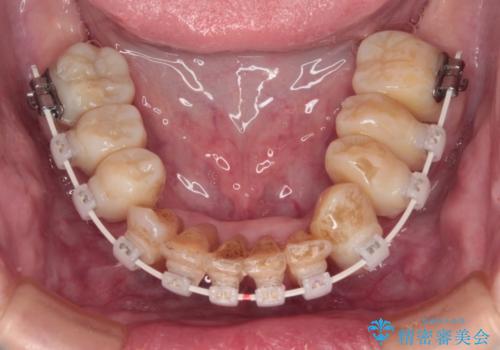

- 矯正装置

- 審美装置

診察を行ったところ、重度歯周病の状態の上に上下の歯列が著しい叢生という状態でした。

歯周初期治療として抜歯や歯槽骨再生治療を行い、さらに歯周ポケット除去を行った後に矯正治療で歯列を整えて行くこととしました。